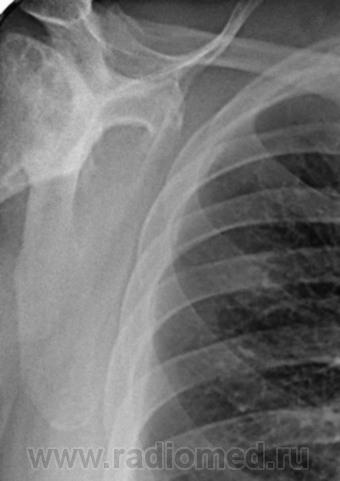

Пациент 60 лет, при прохождении проверочной флюорографии  обнаружены изменения со сторны плечевых суставов.Водитель троллейбуса.Страдает избыточной массой тела, люмбальгией, артороз коленных суставов.Непосредственно жалобы на плечевые суставы в медицинских документах не отражены. Какое будет мнение у коллег?

Пациент жалоб со сторны плечевых суставов не предъяляет и не помнит что бы когда- то что то беспокоило.Данных за сирингомиелию нет.

Александр, конечно надо доснять плечевые суставы... Из того, что есть: видимые отделы плечевых костей выглядят довольно симметрично, хотя слева и похуже, думаю - артроз. Весьма настораживает левая лопатка на предмет хондросаркомы

Снимки плечевых суставов.

Уважаемый Александр, приходиться признать, что на цифровой рентгенограмме легких изменения плечевых суставов видны лучше, чем на "обрезаных" и недоэкспонированых снимках суставов. По имеющимся данным могу только сказать, что деф. артроз с кистовидной перестройкой структуры есть. Под хрящевой опухолью (возможно - хондросаркома) левой лопатки я имела в виду тень, отмеченую красными стрелками, которая в поле снимка не вошла. Моя вина - в силу специфики работы такие узкоформатные снимки давно были вредными, т.к. очень часто патология остается за пределами снимка. Остается рекомендовать рентгенография левой лопатки в прямой передне-задней и косой проекциях, а лучше - КТ...